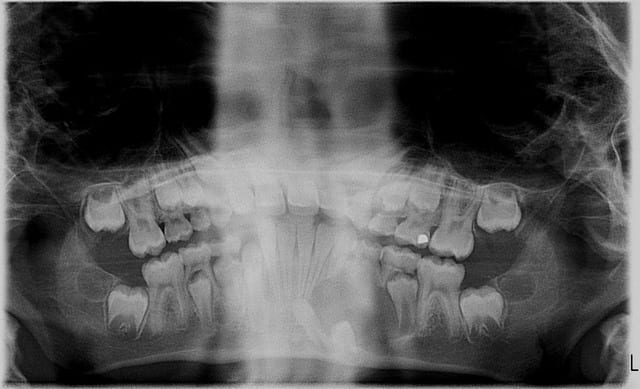

après avoir trafiqué un peu la pano pr mieux voir,je pensais ext de 73 et 74 sous AG (mais ds un service pedo) à cause du curetage du kyste:il me semble trop important,trop bas et la cicatrisation à cet âge trop rapide pr permettre un drainage naturel suffisant

je remets ta pano un peu retravaillée sur photoshop

"